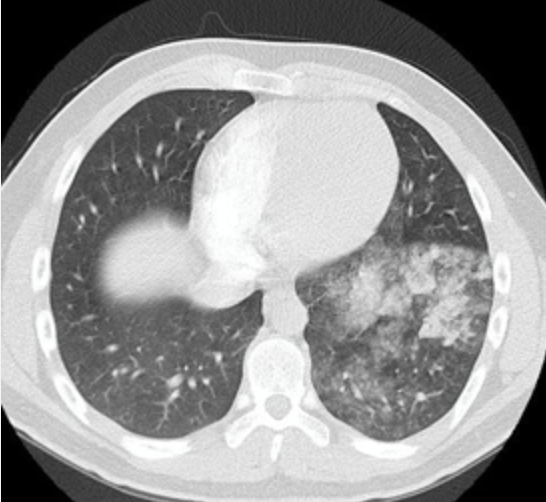

Signos radiológicos de la angiotac

Signo de westermarc y la joroba de hampóton

-Vidreo despulido indica oligohemia